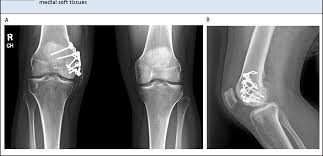

They are called the medial and the lateral femoral condyle, respectively. An imbalance of the muscles around the knee (some muscles are weaker than others.) overuse (repeated bending or twisting) of the knee joint, especially during sports. However, two of the patients had one or more fractures missed when they first presented. The medial femoral condyles are the bony protrusions on the inside edge of the bottom of the femur bone in each thigh. Osteochondritis dissecans (ocd) is an acquired, reversible, idiopathic lesion. Osteonecrosis of the medial femoral condyle presents as a sudden onset of pain on the medial side of the knee. This is associated with a positive bone scan and, frequently, a radiolucent lesion in the subchondral zone. Methods sixteen knees with a small medial femoral. The medial condyle is larger than the lateral (outer) condyle due to more weight bearing caused by the centre of mass being medial to the knee. Medial condyle of femur from wikipedia, the free encyclopedia the medial condyle is one of the two projections on the lower extremity of femur, the other being the lateral condyle. Root tear (radial tear) of the medial meniscus mild or moderate knee arthritis Osteonecrosis of the medial femoral condyle can be treated in a variety of ways depending on the stage of the disease. Of the six patients who had suffered an isolated fracture of their medial condyle, four of the patients had their fractures diagnosed on the first visit.

The radiographs demonstrated abnormal contour of the medial femoral condyle, consistent with an osteochondral defect, and a fabella posterior to the knee. Methods sixteen knees with a small medial femoral. It acts to support a significant amount of the patient's body weight. An imbalance of the muscles around the knee (some muscles are weaker than others.) overuse (repeated bending or twisting) of the knee joint, especially during sports. If there is a fracture (break) in part of the condyle, this is known as a fracture of the femoral condyle. The medial femoral condyle is supplied by a plexus of vessels from the descending genicular artery and the medial superior genicular artery. Damage may also be the result of a direct blow to the knee. Palpable to either side of the knee joint when it is bent, they are known specifically as the medial and lateral femoral condyles.

An articular cartilage injury, or chondral injury, may occur as a result of a pivot or twist on a bent knee, similar to the motion that can cause a meniscus tear. An imbalance of the muscles around the knee (some muscles are weaker than others.) overuse (repeated bending or twisting) of the knee joint, especially during sports. Juvenile ocd lesions have a better healing prognosis than adults. Osteonecrosis of the medial femoral condyle presents as a sudden onset of pain on the medial side of the knee. The radiographs demonstrated abnormal contour of the medial femoral condyle, consistent with an osteochondral defect, and a fabella posterior to the knee. Please see our knee injury protocol for additional information on this topic. Chondral injuries may accompany an injury to a ligament, such as the anterior cruciate ligament. Medial condyle of femur from wikipedia, the free encyclopedia the medial condyle is one of the two projections on the lower extremity of femur, the other being the lateral condyle. In the knee, chondromalacia is usually related to injury, overuse of the knee, and poorly aligned muscles and bones around the knee joint. The motions of the condyles include rocking, gliding and rotating. One presumed mechanism of injury is a stieda fracture (avulsion injury of the medial collateral ligament at the medial femoral condyle). Generally, ocd seems to affect males more commonly than females (between 2:1 and 3:1). According to the hospital for special surgery, the medial femoral condyle is the inside of the knee, and health issues dealing with it can be treated.

A bone fracture at this location is termed a femoral condyle fracture. Tendons and ligaments attach your kneecap to your shinbone and thigh. What is an articular cartilage defect and how is it treated? This is associated with a positive bone scan and, frequently, a radiolucent lesion in the subchondral zone. Damage may also be the result of a direct blow to the knee.